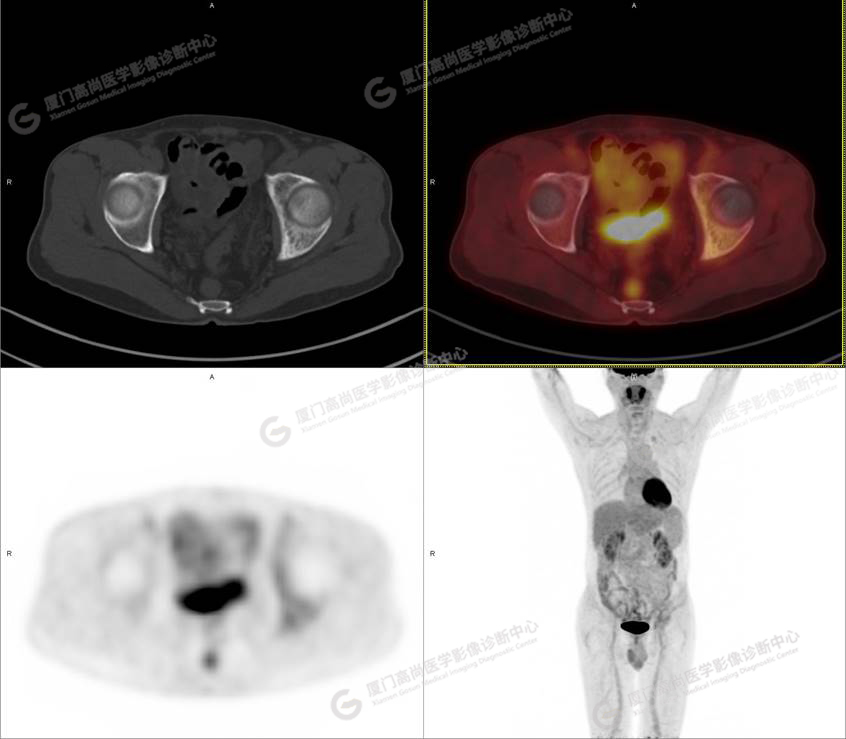

PET/CT影像圖

圖1

圖2

圖3

圖4

PET/CT所見:左側(cè)髂骨、髖臼及恥骨骨質(zhì)密度不均勻增高,CT值約594Hu,邊緣模糊,放射性攝取輕度增高,SUVmax 2.79,周圍軟組織未見明顯異常。